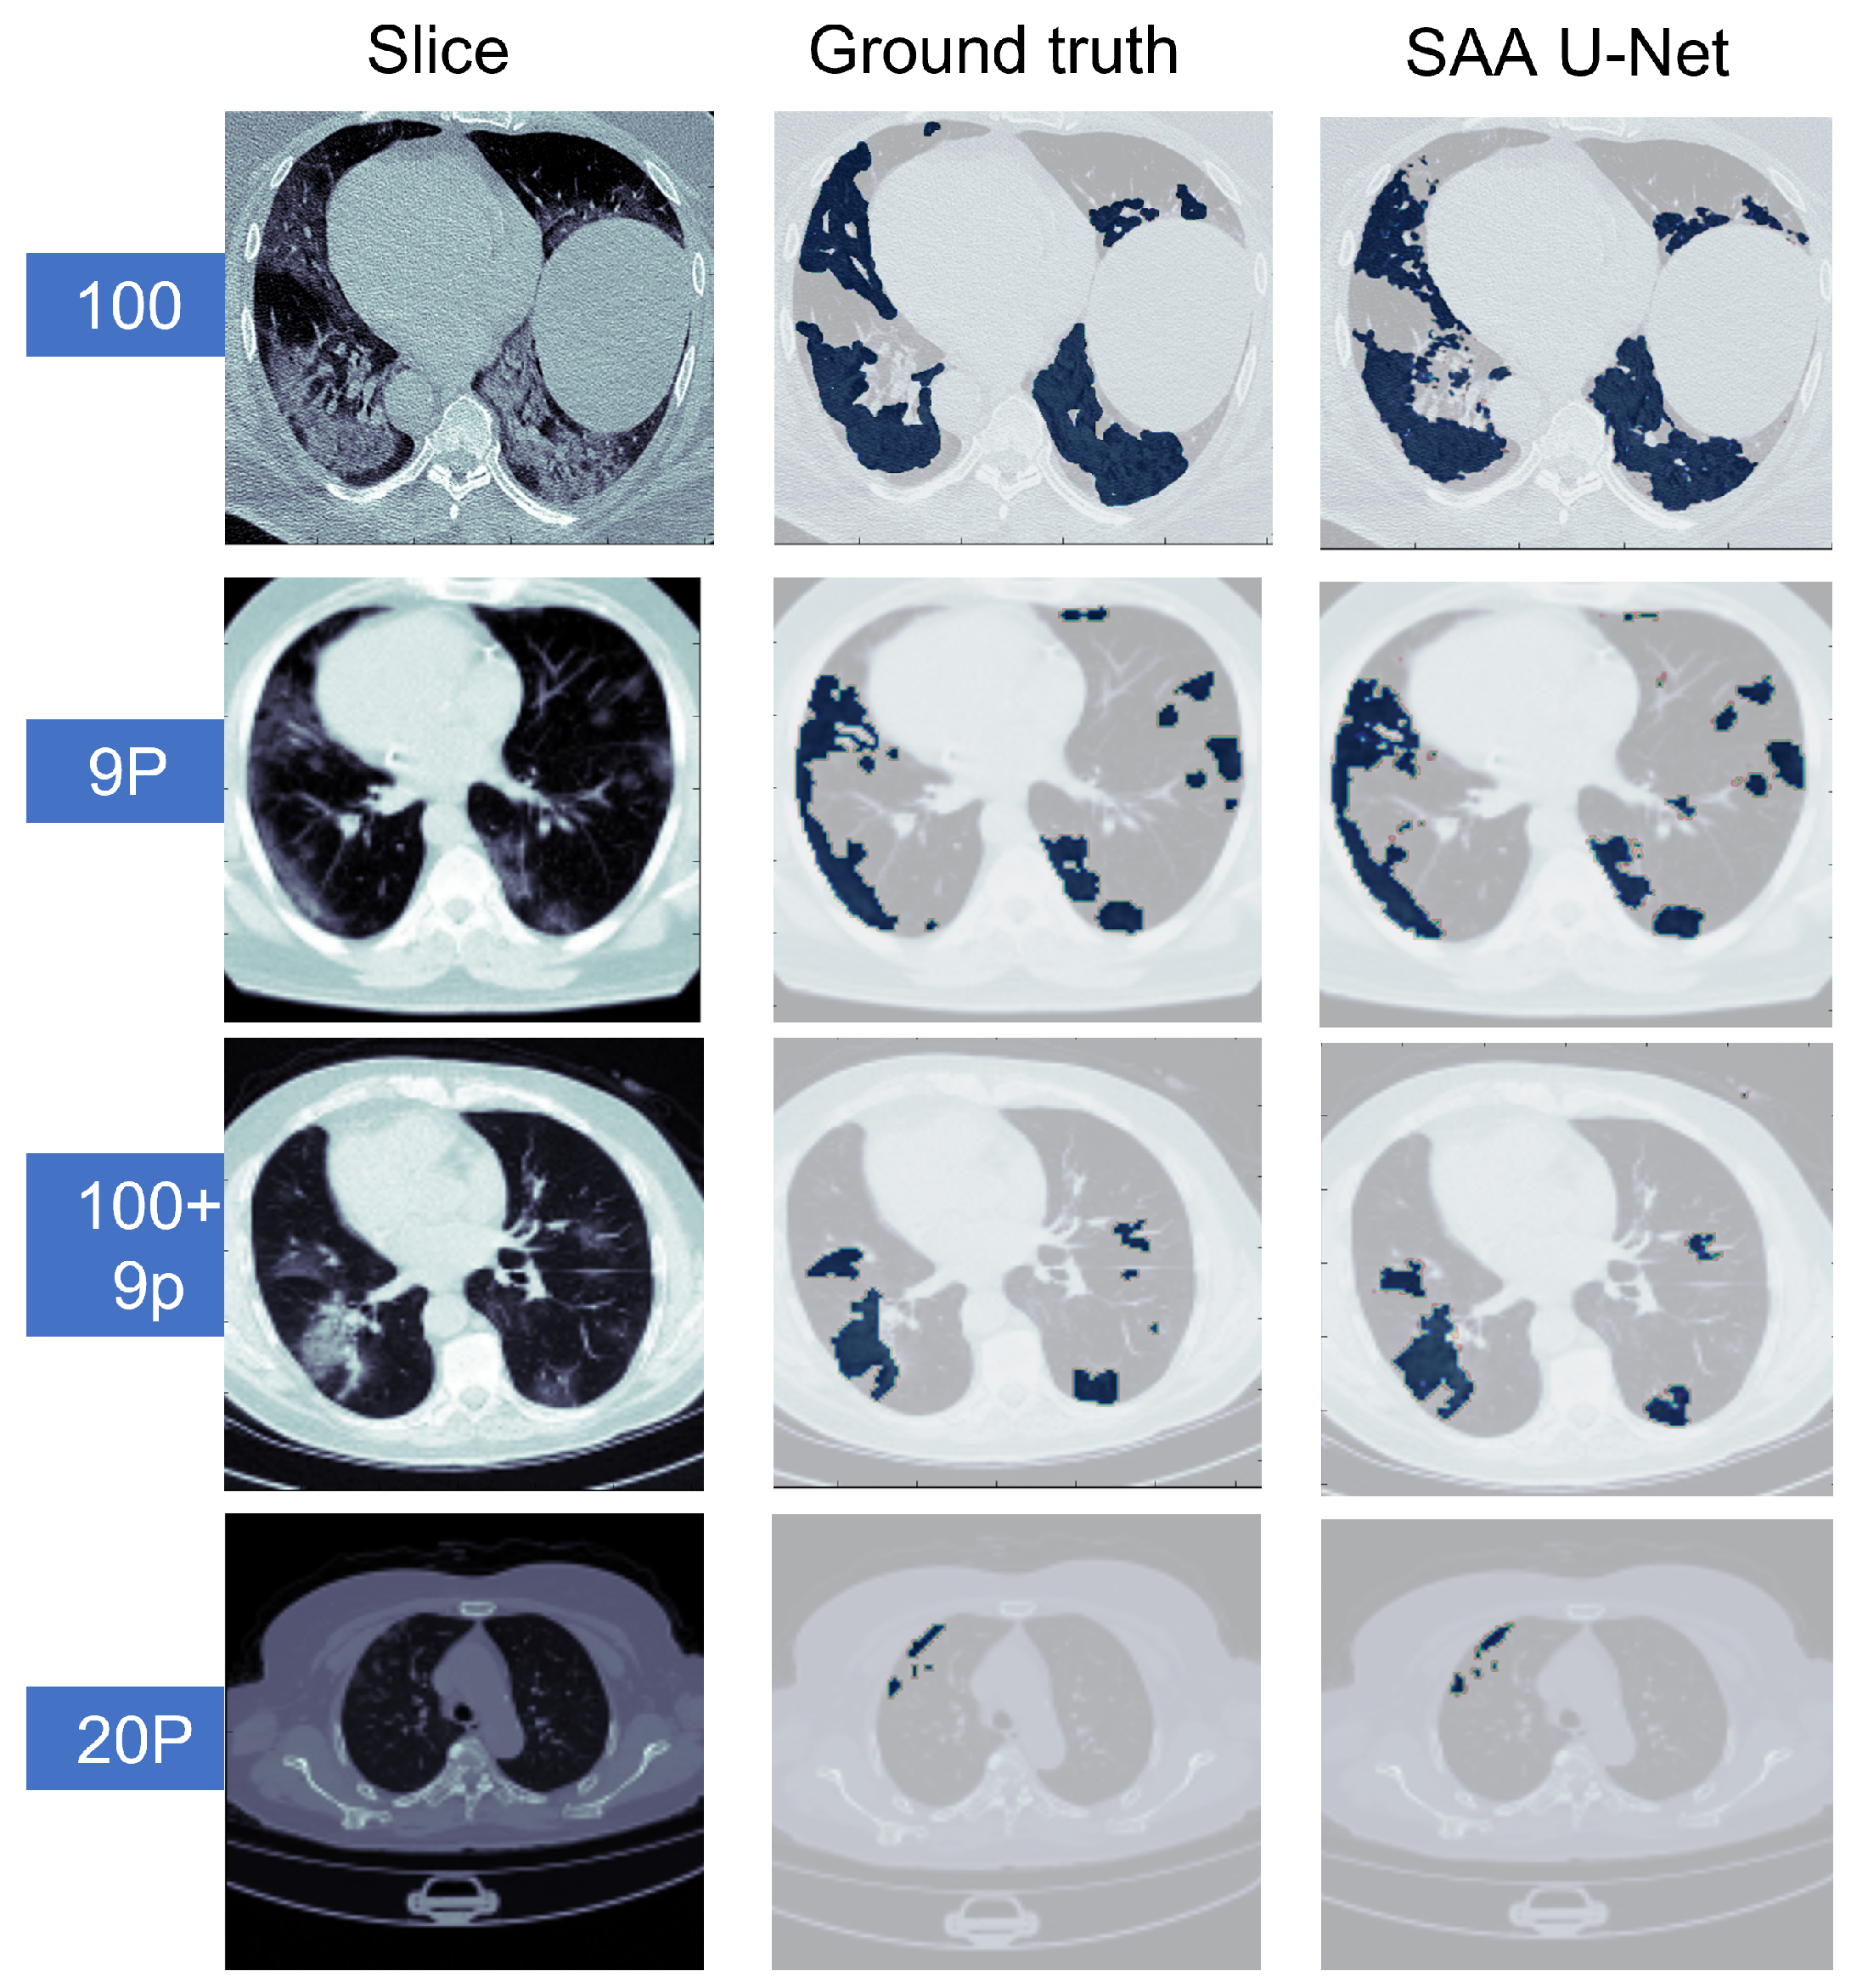

6.2. Binary Class Classification

6.3. Multi-Class Classification